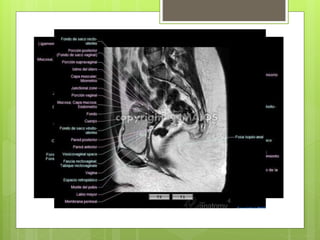

RM PÉLVICA

 Diagnosticar o reconocer la fase de anomalías de

desarrollo como leiomiomas, adenomiosis, neoplasias

vaginales, carcinoma cervical o endometrial, ovarios

poliquísticos u otras masas ováricas.

RM PÉLVICA  Diagnosticaro reconocer la fase de anomalías de desarrollo como leiomiomas, adenomiosis, neoplasias vaginales, carcinoma cervical o endometrial, ovarios poliquísticos u otras masas ováricas.